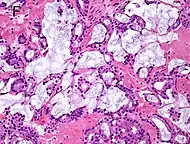

Intraductal carcinoma of the prostate with an infiltrative growth pattern may be morphologically difficult to distinguish from invasive cancer. One focus shows comedonecrosis (arrow), morphologically suggesting Gleason pattern 5 invasive carcinoma (a haematoxylin and eosin, b CK5/6)[20]

Intraductal carcinoma of the prostate with very patchy basal cells identified by immunohistochemistry. At least some of the glands lacking basal cell immunoreactivity represent intraductal rather than invasive carcinoma (a haematoxylin and eosin, b CK 5/6)[20]